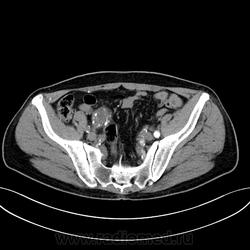

Пациент лежит в кардиологии. Прислали на аортографию. 2 врача УЗИ несколько разошлись в диагнозах: одна видит тромбированную аневризму брюшной аорты, другая - тромбоз нижней полой вены.

А мы получили вот такие красивые картинки.

Шикарно! Тромбированная аневризма инфраренального отдела (над бифуркацией), бифуркации и общих подвздошных артерий, синдром Лериша справа.

И еще маленькая аневризмочка наружной подвздошной слева. Честно говоря, меня больше всего впечатлили коллатерали, благодаря которым клинически он вообще не соответствует исследованию. Конечности теплые, пульсация слабая, но как-то прослеживается...